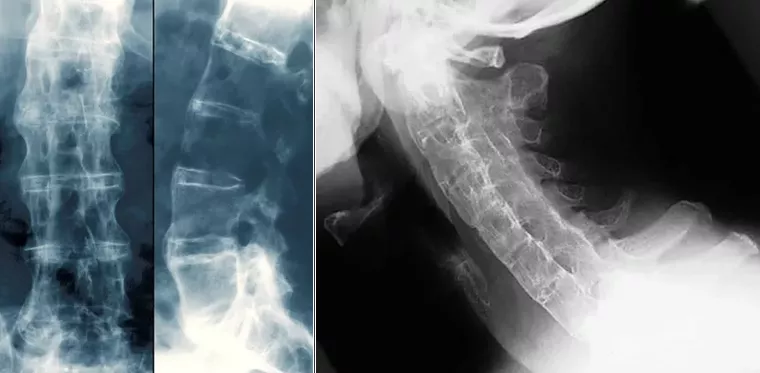

Рисунок 5. Слева и в центре: "Бамбуковый позвоночник" при анкилозирующем спондилите. На данном рентгеновском снимке позвоночника пациента с АС между позвонками выявляется вновь образовавшаяся костная ткань (ярко-белого цвета). В местах, где слияние позвонков завершено, наблюдается формирование «бамбукового позвоночника». Справа: "Бамбуковый позвоночник" при анкилозирующем спондилите. На рентгенограмме шейного отдела позвоночника в боковой проекции показано окостенение шейного отдела позвоночника у пациента с тяжелым давним АС. Позвоночник полностью анкилозирован благодаря синдесмофитам, слитым фасеточным (апофизарным) суставам и параспинальной кальцификации связок.